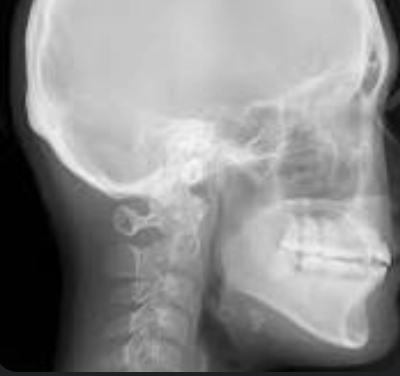

Q

cephalometric

A

Lateral cephalometric